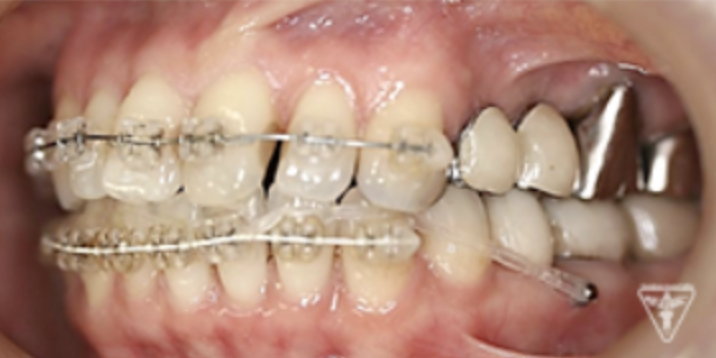

矯正治療

矯正治療による歯軸、叢生改善